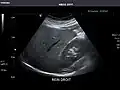

Renal ultrasonography

Ultrasound scan of a kidney (right side)

Ultrasonography of the kidneys is essential in the diagnosis and management of kidney-related diseases. The kidneys are easily examined, and most pathological changes in the kidneys are distinguishable with ultrasound.[7]